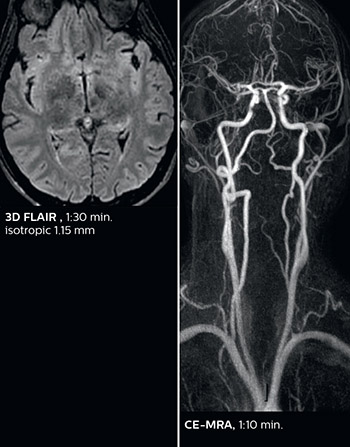

Dr. Savatovsky appreciates the improvements and flexibility that Elition with Compressed SENSE and MultiBand SENSE provides, particularly for stroke patients. “For stroke, it allows us to cut about 5 minutes off of our stroke protocol, or to keep the same acquisition time and get more insights.” The ability to perform more sequences can help in making a swift and confident diagnosis. “For example, our stroke cases usually include the regular sequences that every center does (b1000 diffusion, FLAIR, time-of-flight angiography), but we also image supra aortic vessels, and we can replace a gradient echo sequence with a fast 50-second susceptibility-weighted sequence, and all of this doesn’t add much time. because all the regular sequences are accelerated on Elition.” “The time savings with Compressed SENSE and MultiBand SENSE make it easier to add sequences to give us additional insights. Depending on the context and the first results, we might add a DSC perfusion to assess the ischemic penumbra, an ASL perfusion to help find an alternative cause in case of normal diffusion, or add a high-resolution T1 sequence for a stroke patient, to quickly assess wall imaging in emergency cases. The additional sequences can help improve patient management, because we can already consider some alternative diagnoses if the morphological MRI is normal.”

This is an example of acute ischemic stroke with distal occlusion of the right posterior cerebral artery. Note the improved visibility of the ischemic territory on the diffusion weighted image with high b-value. The 3D FLAIR shows a distal PCA occlusion. The fast SWIp depicts the thrombus on the isolated second echo image. The total scan time (including SmartBrain, preparations and a fast 3D T1w TSE Gd) is 8:00 minutes.